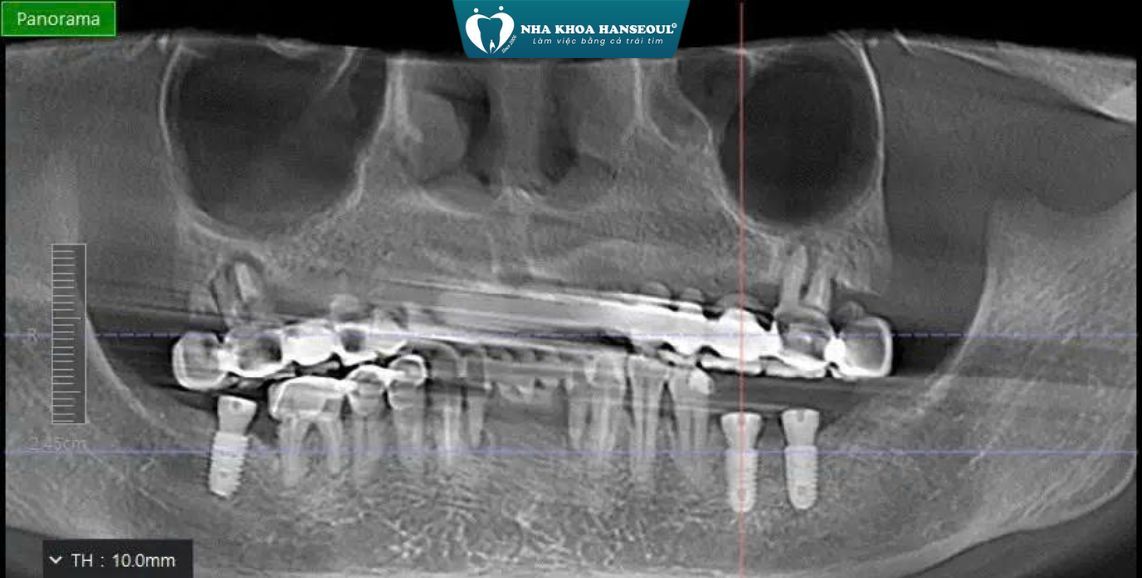

Qua thăm khám lâm sàng và chụp CT ConeBeam 3D, bác sĩ ghi nhận:

- Mất răng vùng hàm dưới: R36 – R37 – R47

- Tình trạng tiêu xương tại các vị trí mất răng do để trống lâu ngày

Cấy ghép 3 trụ Implant tại các vị trí: R36, R37, R47

Ghép xương kết hợp màng sinh học:

- Bổ sung thể tích xương bị tiêu

- Tạo nền xương vững chắc giúp Implant tích hợp ổn định

- Implant tích hợp tốt